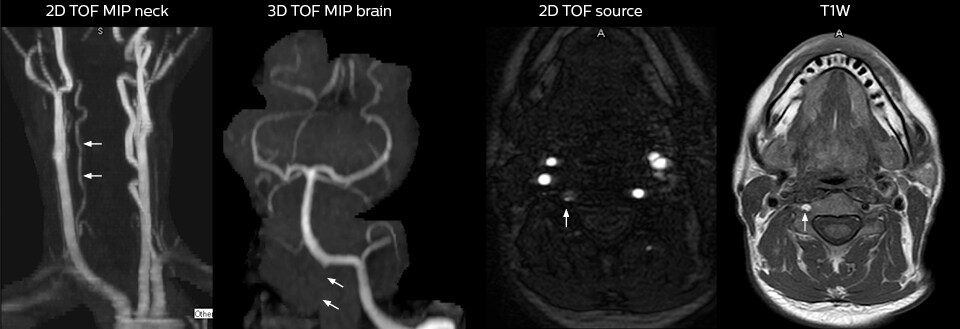

Für Dr. Karis bestehen die nächsten Ziele für die neurologische Notaufnahme in der Umstellung der Untersuchungen für akute Schlaganfall- und TIA-Patienten von CT auf MRT, was eine alternative Managementoption für diese Patienten darstellt. Außerdem wird derzeit die Kooperation mit anderen Abteilungen in die Wege geleitet, was den Nutzen zielgerichteter Untersuchungen mit dem MRT-System in der Notaufnahme noch erhöht. Diese Verbesserungen im Arbeitsablauf können in Kombination mit kürzeren Durchlaufzeiten die Untersuchungsdauer weiter reduzieren.

2. Grimm JM, Schindler A, Schwarz F, Cyran CC, Bayer-Karpinska A, Freilinger T, Yuan C, Linn J, Trelles M, Reiser MF, Nikolaou K, Saam T. Computed tomography angiography vs 3 T black-blood cardiovascular magnetic resonance for identification of symptomatic carotid plaques. J Cardiovasc Magn Reson. 2014;16:84.